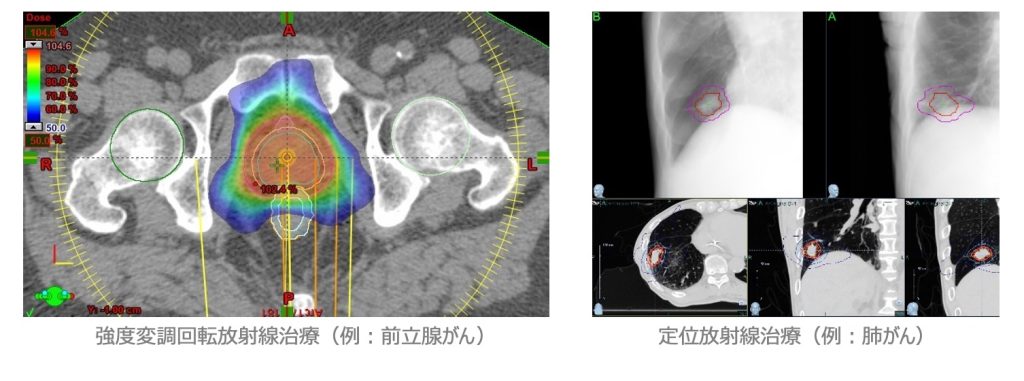

放射線治療

当センターは世界でも最先端の高精度外部照射装置と密封小線源治療装置を備えた我が国屈指の放射線治療施設です。

放射線治療はその精度を高める事により、正常組織に対する副作用を軽減し、かつ腫瘍の制御を従来よりも向上させる事が出来ます。更に手術や化学療法(抗がん剤治療)を併用する事によって、症状が進行した症例に対しても安全で効果的な治療を行う事が出来ます。

当センターの放射線治療は、放射線治療専門技師、放射線治療品質管理士の認定を受けた診療放射線技師を中心とし、放射線治療品質管理室とともに日々の精度管理のもと治療を担当しています。

外部照射の中には、高精度放射線治療として強度変調放射線治療および定位放射線治療があります。従来型の放射線治療と比較して、先進的な照射技術です。たとえば前立腺の治療を行う患者さんには、隣接する膀胱、直腸への影響を避けながら放射線を照射することができます。また、肺がんの患者さんには、正常な肺組織を避けながら、腫瘍に限局し放射線を集中できます。これらの治療法は当センターで盛んに行われています。